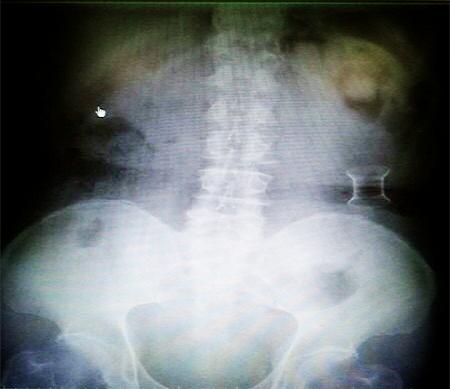

受試患者在結(jié)腸端端吻合術(shù)中,使用我司新研制產(chǎn)品達(dá)到了理想的預(yù)期效果。患者術(shù)后7天、14天X光片顯影,可降解腸道支架均能按研制設(shè)計的預(yù)期時間節(jié)點保持應(yīng)有強(qiáng)度,術(shù)后21天X光片顯示可降解腸道支架已完全破碎,并排出體外。在整個試驗過程中,病患無任何不良反映,耐受良好。